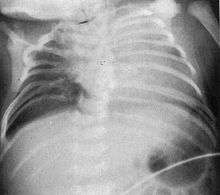

| Radiograph depicting typical skeletal features of Jarcho-Levin syndrome, subtype spondylothoracic dysplasia. Note fanlike configuration of the ribs, with extensive posterior fusion, along with multiple vertebral segmentation defects. | |

Spondylothoracic dysplasia, or STD, has been repeatedly described as an autosomal recessively inherited condition that results in a characteristic fan-like configuration of the ribs with minimal intrinsic rib anomalies. Infants born with this condition typically died early in life due to recurrent respiratory infections and pneumonia due to their restricted thorax.[3][5][18] Recently, a report[13] has documented that actual mortality associated with STD is only about 50%, with many survivors leading healthy, independent lives.